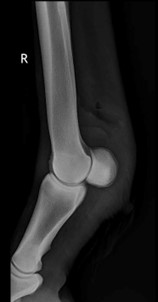

To accurately assess the depth, extension and size of acute wounds, clipping and cleaning are essential, particularly as the wound frequently extends further than anticipated before clipping (Figures 1 and 2). The use of radiographs and ultrasound can help determine involvement of, and damage to, underlying structures, demonstrate the presence of foreign bodies and give an indication of penetration of adjacent synovial structures. Gas within synovial structures may be observed as radiolucencies on radiographs (Figure 3) or hyperechogenicity on ultrasound scan, but they must be differentiated from superimposed subcutaneous gas/air within fascial planes (Figures 4 and 5).